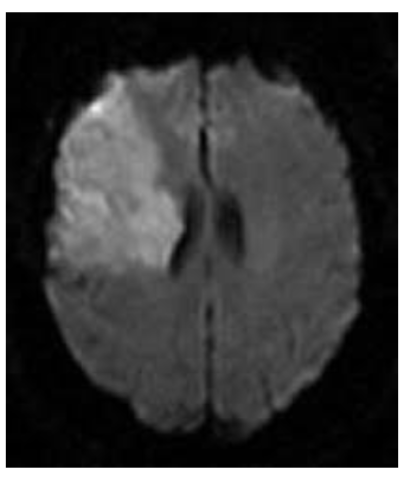

What type of stroke is shown on the provided DWI image?

A

watershed stroke - string of pearls sign

between MCA & ACA territory, but all in one hemisphere

20

Q

This watershed stroke suggests what etiological cause?

ipsilateral carotid stenosis & hypovolemic state

loss of blood pressure → loss of perfusion → w/ stenosis lose have stroke in area between MCA & ACA territory